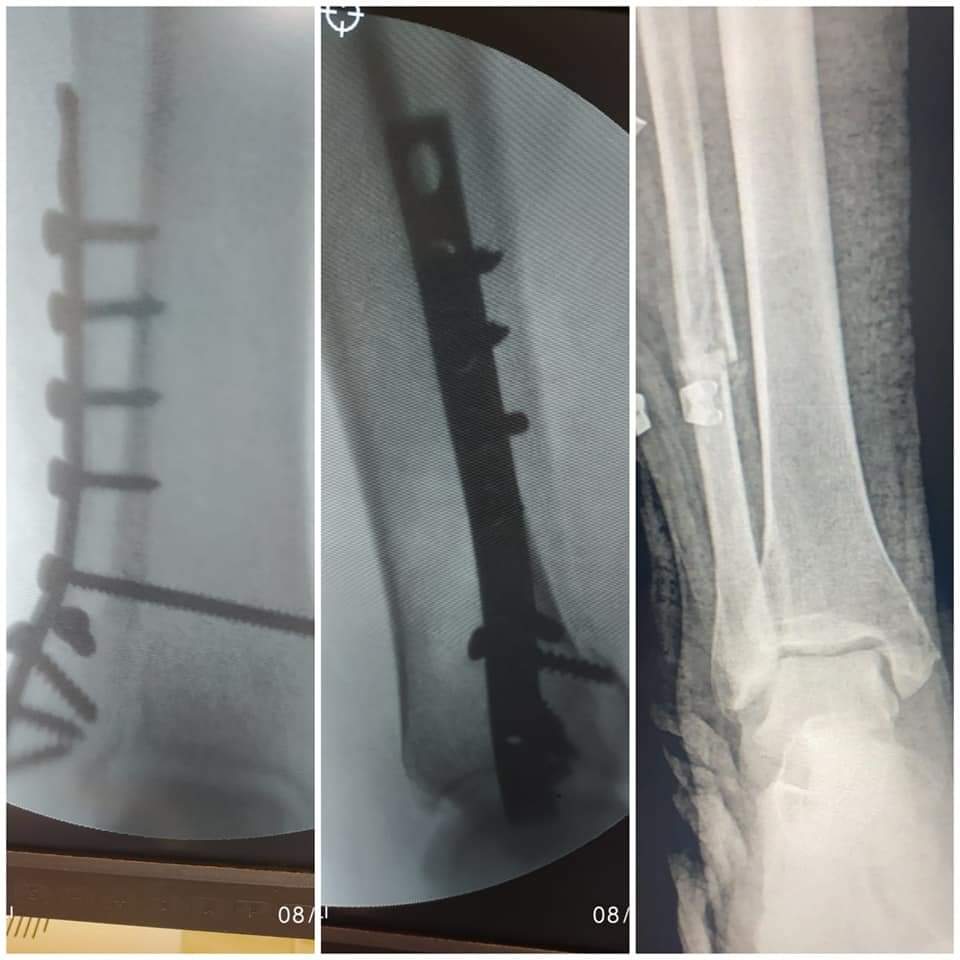

في سياق آخر وتنفيذاً للمبادرة الرئاسية بالقضاء علي قوائم الانتظار الخاصة بالعمليات الجراحية، قام الفريق الطبي بقسم العظام بالمستشفي بإجراء ١٤ عملية جراحية خلال الأسبوع الماضي، وذلك بعد إجراء كافة الفحوصات الطبية والمعملية، والأشعات اللازمة للمرضي، وتنوعت العمليات بين "كبرى، ومتوسطة، وذات مهارة"، لتشمل عملية رد مغلق مع تثبيت كسر مضاعف مفتوح بعظمتي الكعبرة والزند، وعملية رد مغلق مع تثبيت كسر مفتت مفتوح بأعلى النترء البعيد لعظمة العضد، وعملية رد مفتوح مع تثبيت كسر بنهاية عظمة الشظية بالساق بواسطة شريحة ومسامير، وعملية رد مغلق مع تثبيت كسر بمنتصف عظمة القصبة بالساق بمسامير معدنية مرنة، وعملية رد مغلق مع تثبيت كسر بأسفل عظمة الساق بأسلاك معدنية مع رد مفتوح، وتثبيت كسر بأسفل عظمة الشظية، وعملية رد مغلق مع تثبيت بأعلى النتوء البعيد لعظمة العضد، وعملية رد مفتوح مع تثبيت كسر مفتوح مضاعف بعظمة العضد، وعملية رد مغلق مع تثبيت لكسر مفتت مضاعف مفتوح بأسفل عظمة القصبة بالساق بواسطة مثبت خارجي، وعملية إصلاح وتر أكيلس مقطوع كليا، وعملية رد مغلق لخلع متكرر بأصابع القدم، وعملية استخراج جسم غريب من القدم تحت الأشعة المرئية CARM، وعملية تنظيف ورتق وإصلاح جرح متهتك بمنتصف عظمة القصبة بالساق، وعملية رد مغلق مع تثبيت كسر مفتت بالنهاية البعيدة لعظمة الكعبرة....